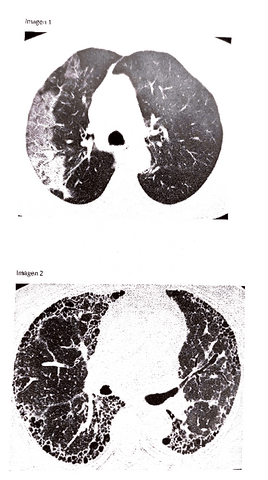

Apuntes - Respiratorio-Patologia-organos-sistemas-II.pdf

113 páginas